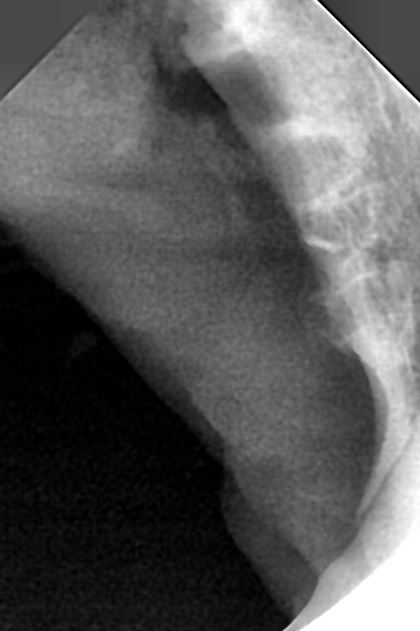

| 치료과정 | 꼬리는 상태가 조금 나아졌다싶으면 사라졌다가 매우 악화된 모습으로 나타나기를 반복하고는 했다 더이상 약도 큰 효과가 없었고 피섞인 침을 흘리며 음식물을 먹지 못하며 점점 상황이 심각해져가서 전발치및 입원치료가 필요성을 느끼고 치료지원신청을 하게 되었다. 어느 날 갑자기 사라져서 걱정했는데 다행히 다시 나타나서 구조하게 되었다. 치료지원신청 당시 미리 신청해두었던 동물병원으로 이송했는데, 선생님께서 꼬리는 당장 전발치를 감당할수 있는 체력이 아니라고 하였다. 조금이라도 더 나은 체력상태를 만들기 위해 꼬리는 얼마간 수액을 맞고 체력보충을 하고나서 전발치를 하게되었다. 여태까지는 유석 동물병원에서 전발치 수술+목구멍레이저를 함꼐하는 치료프로토콜이었는데, 이번에는 목구멍레이저는 실시하지 않는 곳이어서 그런건지,아니면 꼬리의 상태가 오랫동안 (1년이상으로 추측) 너무 심각해서 그런건지 전발치를 하고나서, 충분한 입원치료를 하고나서도 침을 흘리는 증상이 지속되었고 방사를 할 수 있는 건강상태로 쉽게 회복되지 못했다. *엑스레이 사진은 동물병원에서 주신 전발치 방사선과 전발치 이후 케어 과정. |